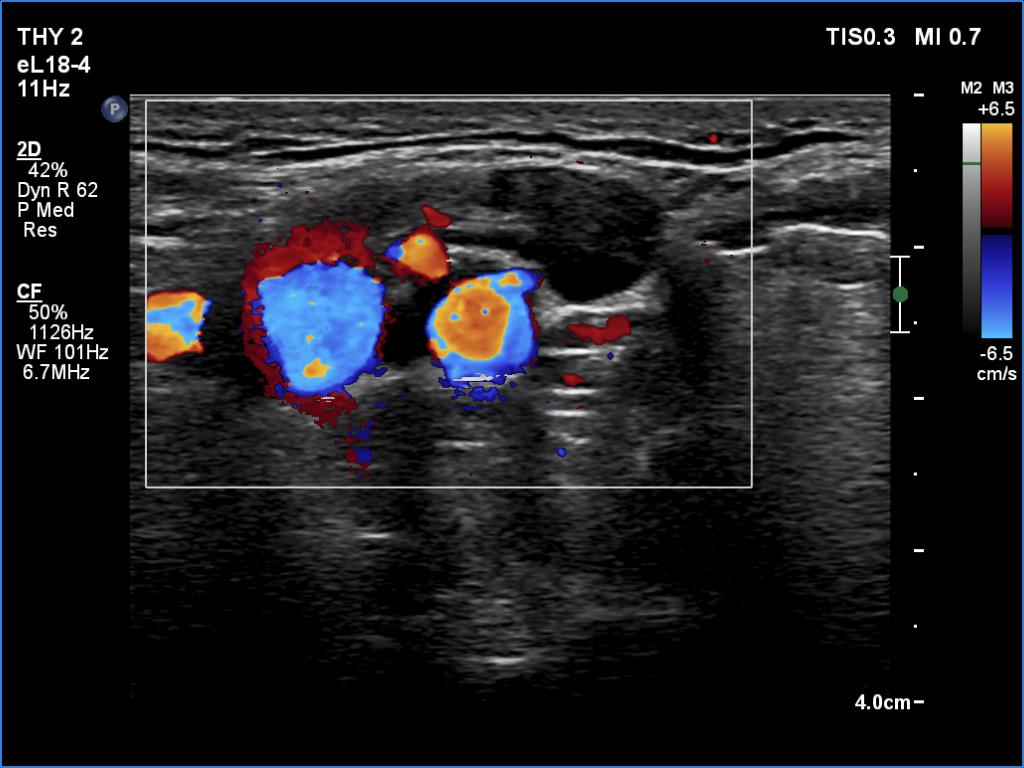

Follow-up examination 8 years later (4th and 5th rows of images):

Clinical data: The patient was referred for evaluation of a continuously increasing thyroglobulin level which resulted in 2.86 ng/mL, 5.74 ng/mL and 20.1 ng/mL, at the 2-yr, 5-yr and 7-yr follow up. Cytology of enlarged lymph nodes, multiple CT-scans and PET-CTs failed to reveal recurrence.

Palpation: There were two palpable, firm but freely moveable masses in the right and left submandibular area.

Hormonal examination: indicated euthyroidism with TSH 2.95 mIU/l on daily 125 microgram levothyroxine. Thyroglobulin was 15.4 ng/mL, anti-hTg was below 20 U/mL.

Ultrasonography revealed hypoechoic discrete lesions in both thyroid lobes. The lesions presented microcalcifications. Corresponding to the palpable mass in the right submandibular region, a reactive-type regular lymph node was found. There was an enlarged lymph node in the left submandibular region. The node had a regular hilum but displayed a heterogeneous pattern.

Cytology was performed from both lymph nodes and from the lesion in the left thyroid bed. FNA resulted in non-diagnostic report from the lesion in the left thyroid bed while cytology of the submandibular lymph nodes showed patterns of a benign, reactive-type lymph node.

Wash-out thyroglobulin levels were 0, 81.1 and 104.9 ng/mL, right submandibular lymph node, left thyroid bed lesion and left submandibular lymph node, respectively.

Comment. Until the final histological examination is completed, I would like to draw attention to two things. One is the heterogeneity of the left lymph node and the other is the size and structure of the lesions in the thyroid beds - these features are suspicious of thyroid cancer.